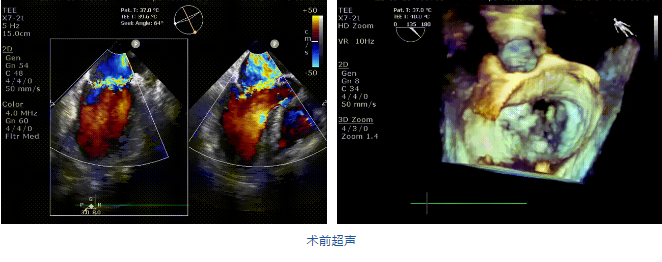

接受治療的是一例二尖瓣重度反流的患者,主訴“突發(fā)間歇性胸悶,氣急6天”。術(shù)前超聲提示:1.二尖瓣脫垂伴重度關(guān)閉不全(瞬時(shí)量30ml);2.左心、右房增大(左房容積110ml,左室容積129ml,右房容積55ml);3.左室收縮功能正常?;颊咴诔浞謽?biāo)準(zhǔn)化藥物治療后(GDMT)仍然癥狀明顯,韓林教授及其團(tuán)隊(duì)唐楊烽教授,以及心超科的周廣為醫(yī)生決定使用我國創(chuàng)新器械JensClip為患者進(jìn)行二尖瓣緣對緣修復(fù)手術(shù)。

在阜外醫(yī)院潘湘斌教授團(tuán)隊(duì)的支持下,手術(shù)經(jīng)股靜脈-房間隔入路,采用全身麻醉插管,在TEE和DSA引導(dǎo)下完成房間隔穿刺。置入JensClip瓣膜夾系統(tǒng)后,在左房調(diào)整瓣膜夾的位置和軸向,后進(jìn)入左室,在TEE引導(dǎo)下捕捉二尖瓣前后瓣葉,并關(guān)閉瓣膜夾。經(jīng)TEE反復(fù)確認(rèn)手術(shù)效果后最終鎖定并釋放瓣膜夾。術(shù)后即刻超聲顯示瓣膜夾位置穩(wěn)定,功能良好,二尖瓣反流由術(shù)前4+減少至微量,手術(shù)圓滿成功。